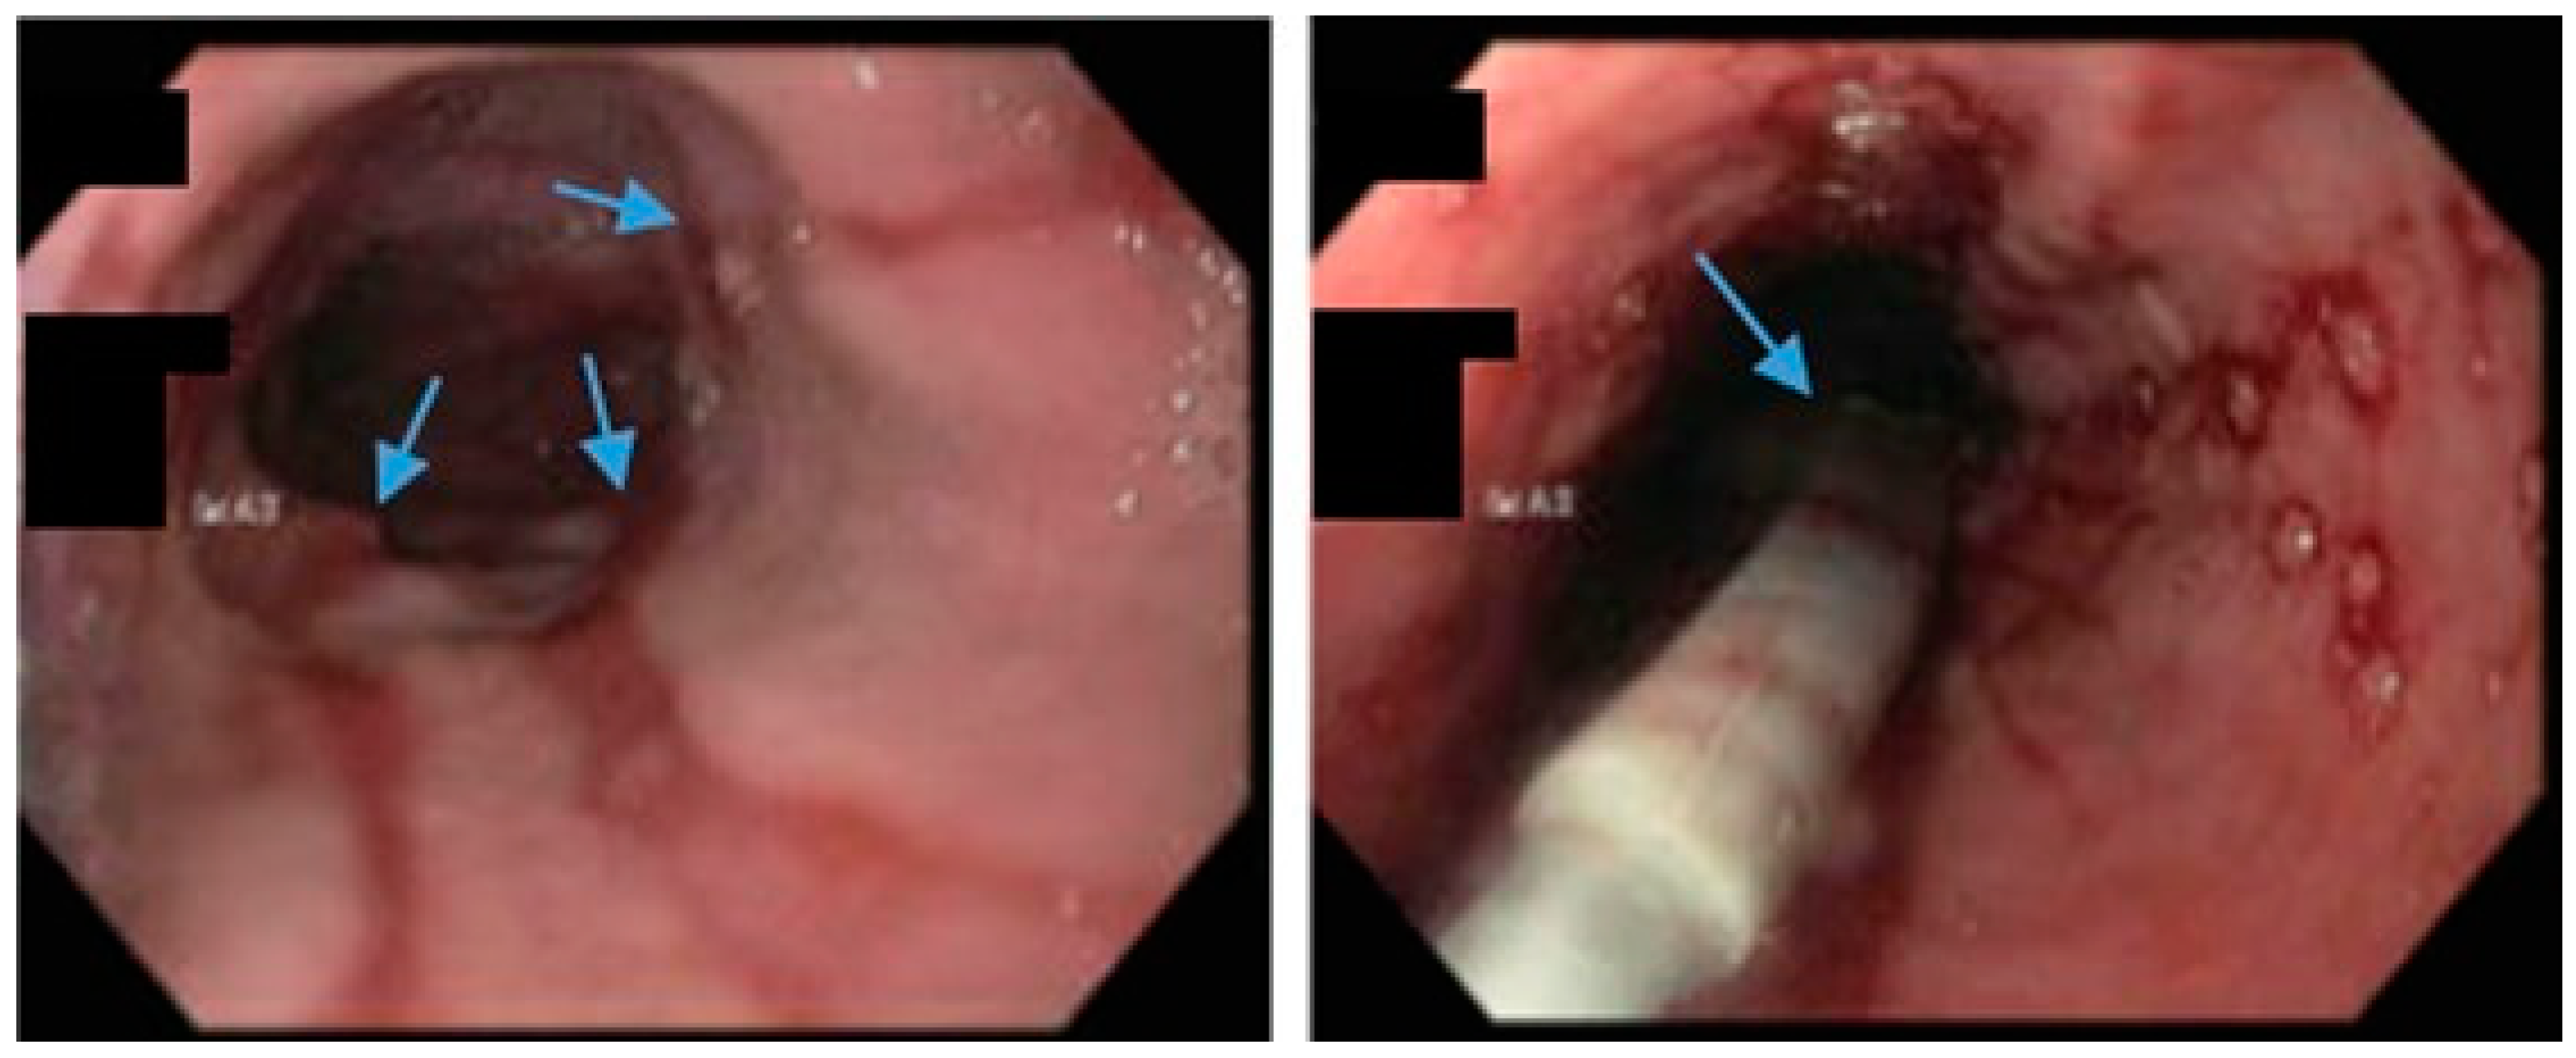

Figure 5.

Upper endoscopy demonstrates Los Angeles Grade C esophagitis in a patient following sleeve gastrectomy (arrows, left). A Bravo™ capsule was placed endoscopically for pH monitoring (Medtronic, Minneapolis, Minnesota, USA) (arrow, right).

An international expert panel on sleeve gastrectomy reported that 52.5% of general surgeons and 23.3% of bariatric surgeons considered GERD as a contraindication to SG [65]. According to a multi-society consensus statement, SG should not be performed as an antireflux procedure [66]. Data suggest that patients with a BMI > 35 and medically refractory GERD should be considered for RYGB rather than fundoplication due to the following: an increased risk of hiatal hernia and GERD recurrence with fundoplication in patients with BMI > 35, as well as an additional weight loss and metabolic benefit conferred by RYGB to address a myriad of comorbidities [66,67,68,69,70].